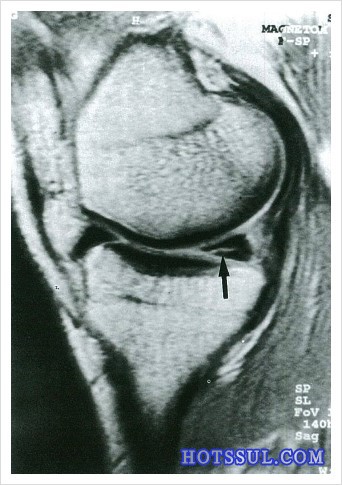

위에 사진처럼 민간병원 의사가 연골찢어진걸 보여줌ㅋ